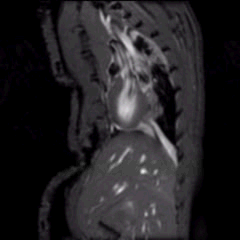

Les plateformes du CRI sont équipées d’une technologie évolutive de pointe dans les domaines de la microscopie électronique, la Cytometrie, la physiophatologie animale et la Biochimie.